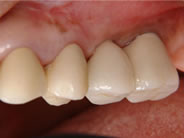

左上顎に骨を作って(上顎洞底挙上術)インプラントを入れました。

入れ歯の必要がなくなりました。

インプラントを入れることによって、自分の隣の歯を削る必要がなくなります。

Bridgeを入れるよりも良い方法です。

5年以上経過しています。

骨の吸収も全くありません。